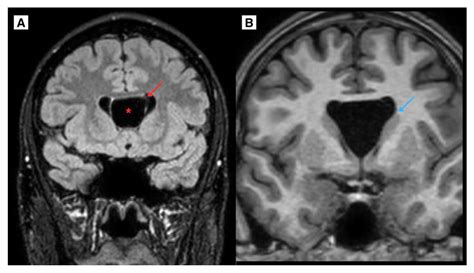

Diagnostic imaging techniques, such as magnetic resonance imaging (MRI), are essential for visualizing the Cavum Septum Pellucidum and assessing its size and shape. MRI provides high-resolution images of the brain, allowing clinicians to detect abnormalities in the Cavum Septum Pellucidum and other structures.

| Magnetic Resonance Imaging (MRI) | Provides detailed images of the brain's soft tissues | Assessing the size and shape of the Cavum Septum Pellucidum |

MRI is the preferred imaging technique for evaluating the Cavum Septum Pellucidum due to its high resolution and ability to differentiate between soft tissues. CT scans and PET scans may also be used in specific clinical contexts, but they are less commonly employed for assessing the Cavum Septum Pellucidum.